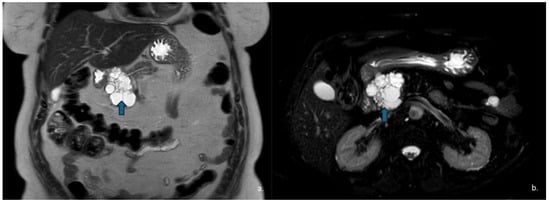

Figure 9.

MRI of a 37-year-old woman shows a lesion in the pancreatic head (arrow) with intermediate signal intensity on T2-w HASTE sequences (a) and mild enhancement of the solid component on dynamic arterial-phase sequence (b). Endoscopic ultrasound suggested the diagnosis of a solid pseudopapillary epithelial neoplasm (SPEN).

Figure 10.

The same patient as in Figure 7 underwent Contrast-Enhanced MRI, which showed a lesion (arrow) with inhomogeneous signal in the T2w—HASTE sequences (a) and areas of restricted diffusion in DWI and ADC maps corresponding to the mural nodules. (b,c) The patient subsequently underwent surgical resection, and histopathology confirmed a degenerated mucinous cystadenoma.